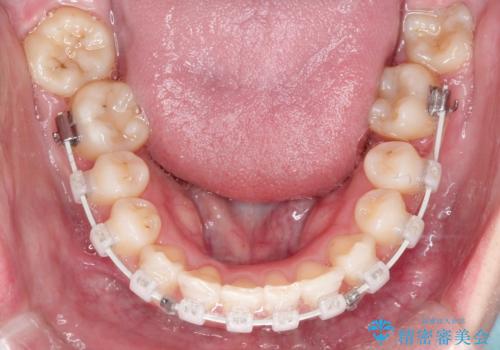

ワイヤー矯正を用いて、欠損部の閉鎖を目的とした後方からの歯の挺出・移動を行いました。

特に、親知らずを活用し、奥歯の噛み合わせを構築することに重点を置きました。

治療の途中で、1年間ご来院が難しい期間があり、当初の予定より治療期間は延長しましたが、

最終的には予定通りインプラントを使用せずに欠損部を閉鎖し、咬合も安定させることができました。